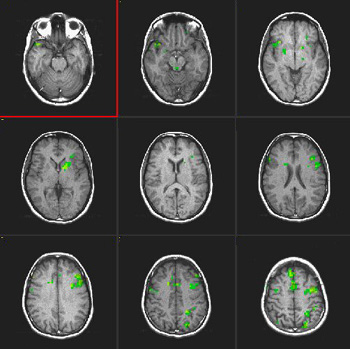

Fluency of Verbs

| Subject | Right handed, 24 year-old woman | ||||||

| Paradigm | ON: Generate verbs related to nouns (objects) OFF: Count the letters of presented words | ||||||

| Statistics |

| Activation | Broca's area and left SMA are depicted. Some activation appears in the left hippocampal formation and visual areas. This last activation could be explained as the effect of picturing the objects given during the "ON" condition. There is also activation in the right cerebellum and left inferior temporal gyrus. |